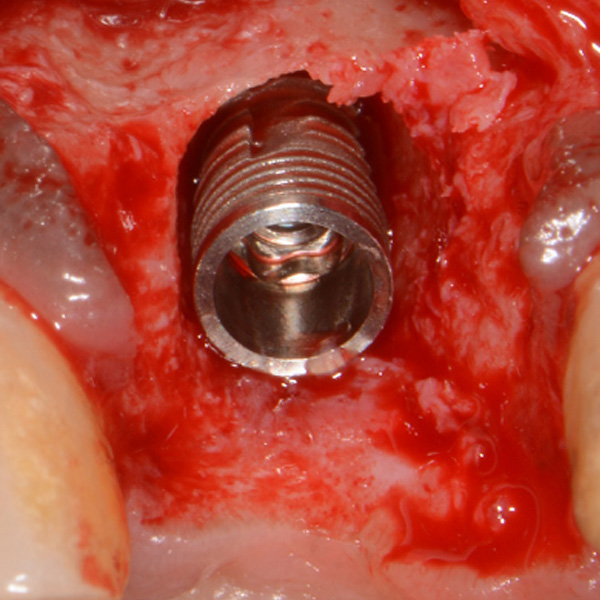

Immediate Dental Implant Placement

Tooth 14 slightly increased mobility, tenderness and bite pain. Suspected root fracture